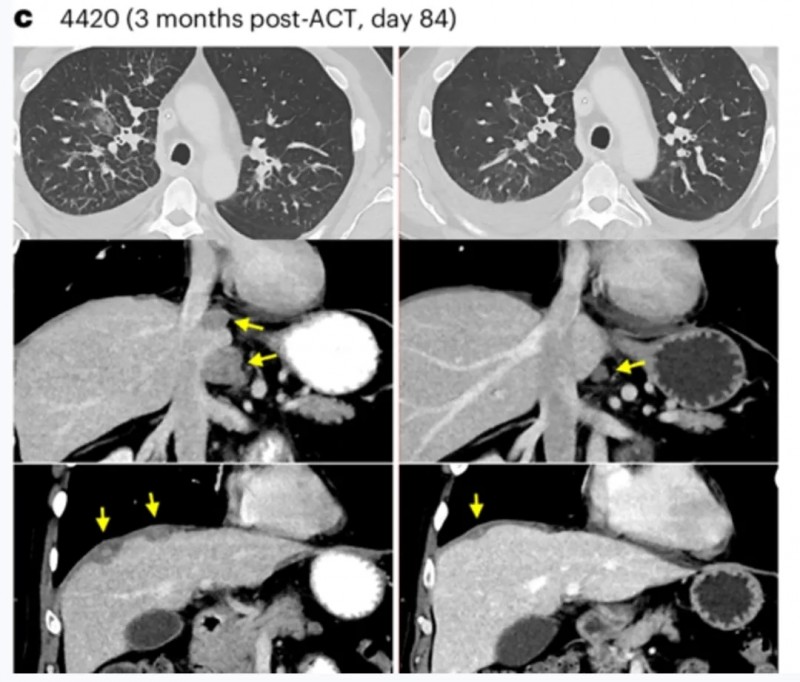

患者4420(转移性结肠癌)治疗后,经支气管镜证实的右肺淋巴管炎(详见下图c上图,轴位)、腹膜后淋巴结及肝周肿瘤(详见下图c中图、下图,冠状位)均实现消退。

▲图源“Net Med”,版权归原作者所有,如无意中侵犯了知识产权,请联系我们删除